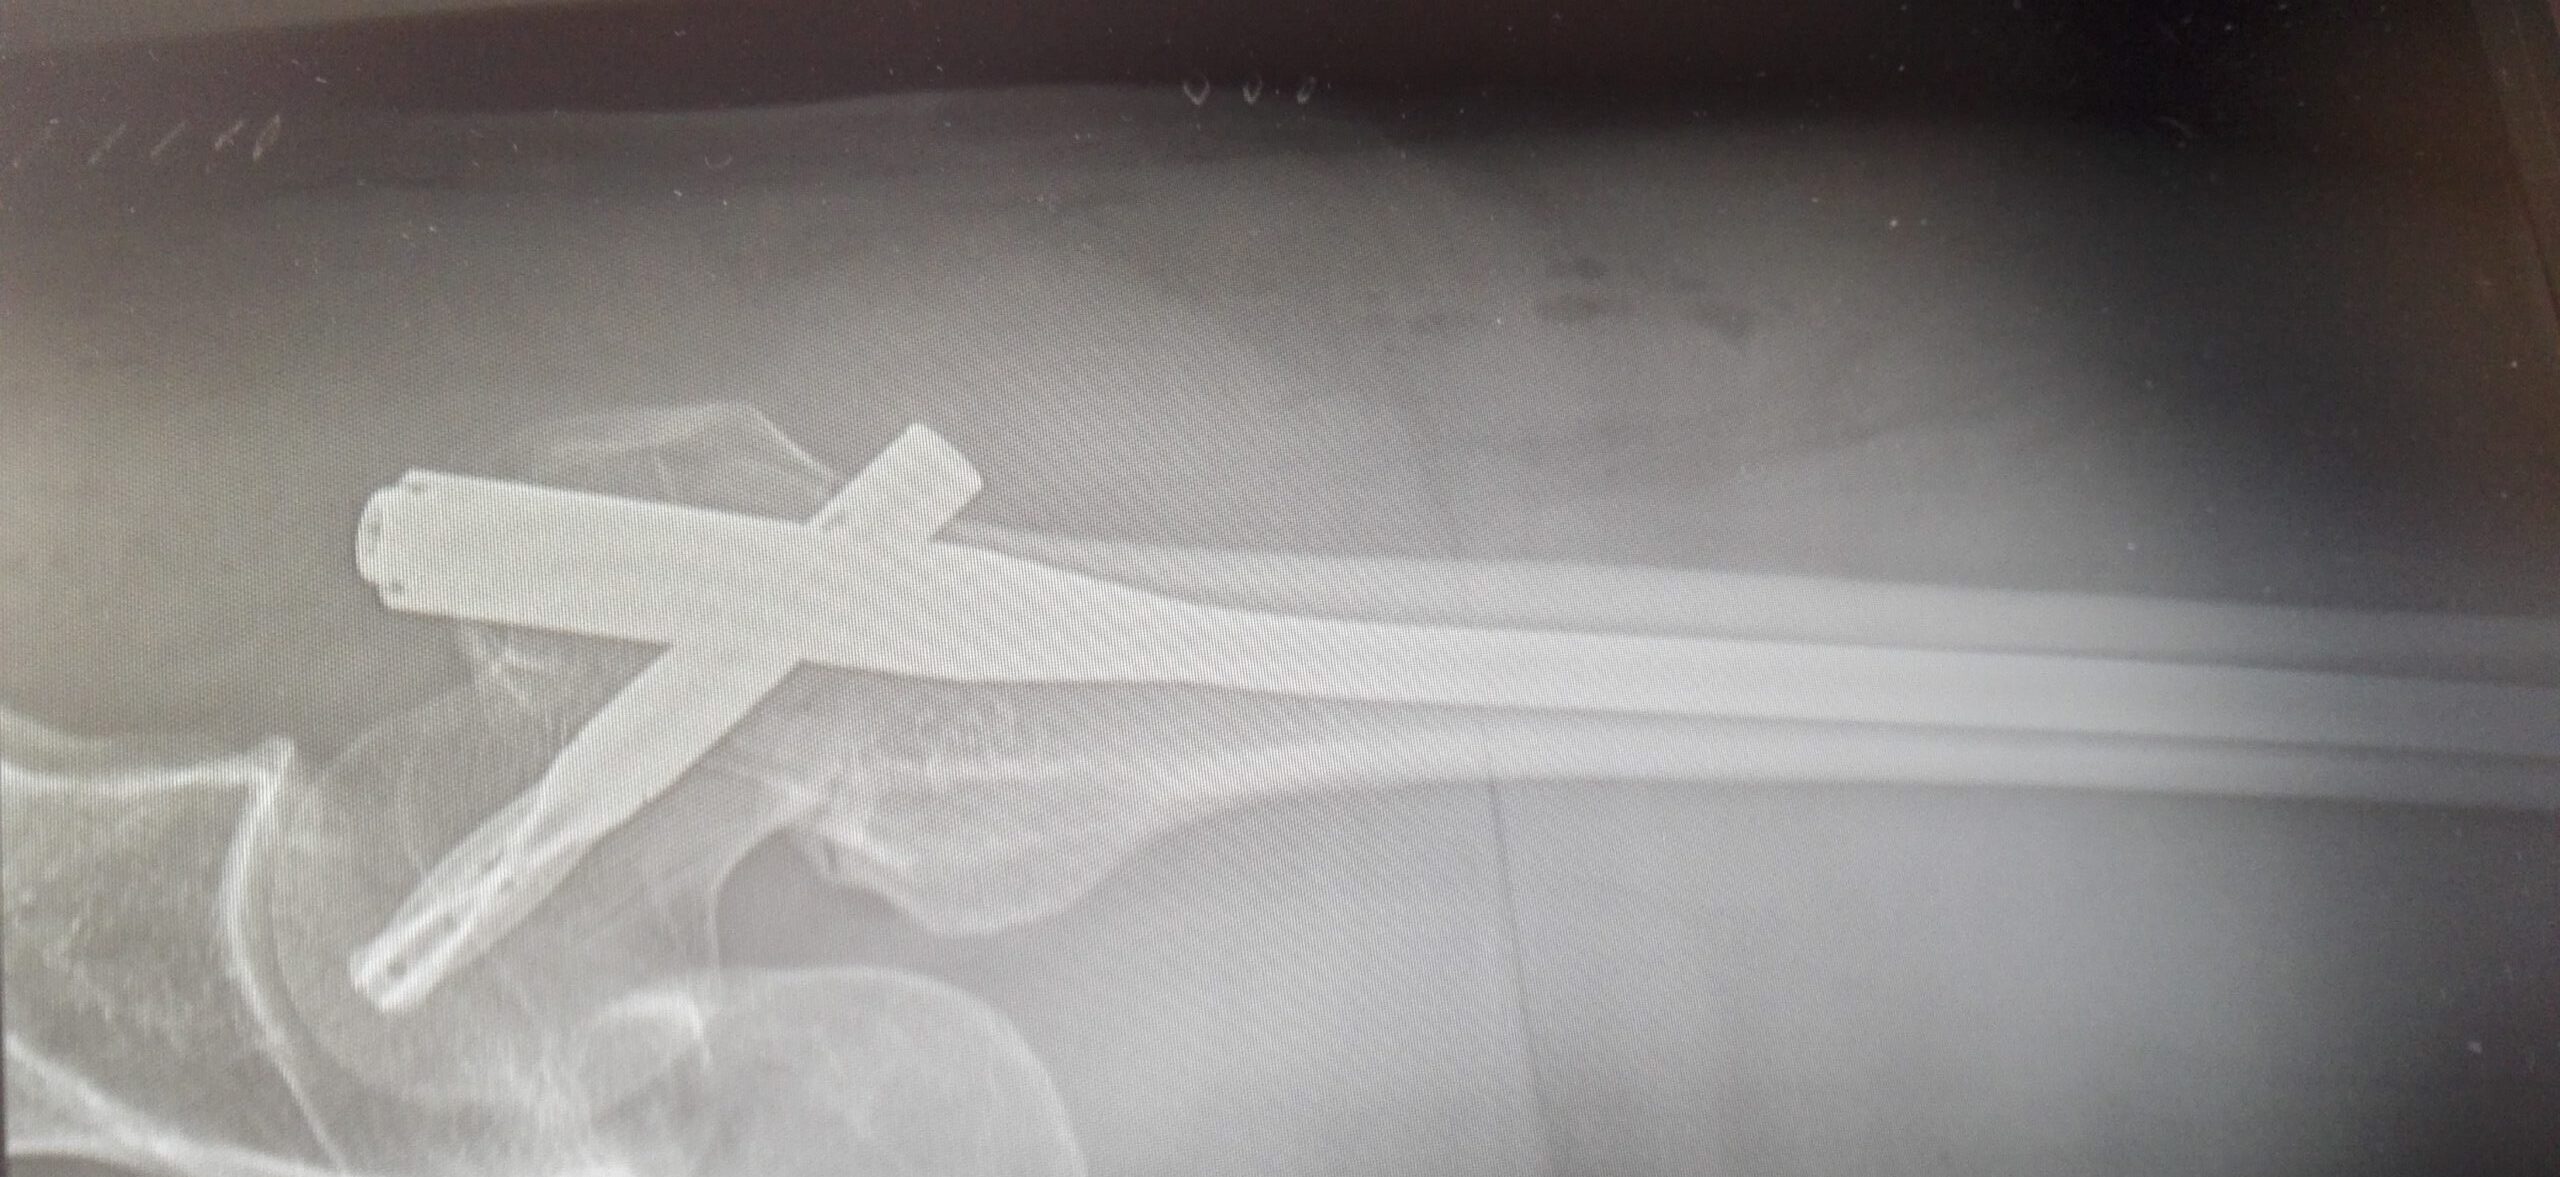

Den efterfølgende skanning viser, at Alexandar har knogleskørhed. Han får sat et marvsøm ind i venstre lårbensknogle, og kan allerede stå op dagen efter. Men marvsømmet er ikke uden gener. Et mindre stykke af marvsømmet går ud af knoglen og skaber irritation af muskulatur og fedtpude med smerter til følge.